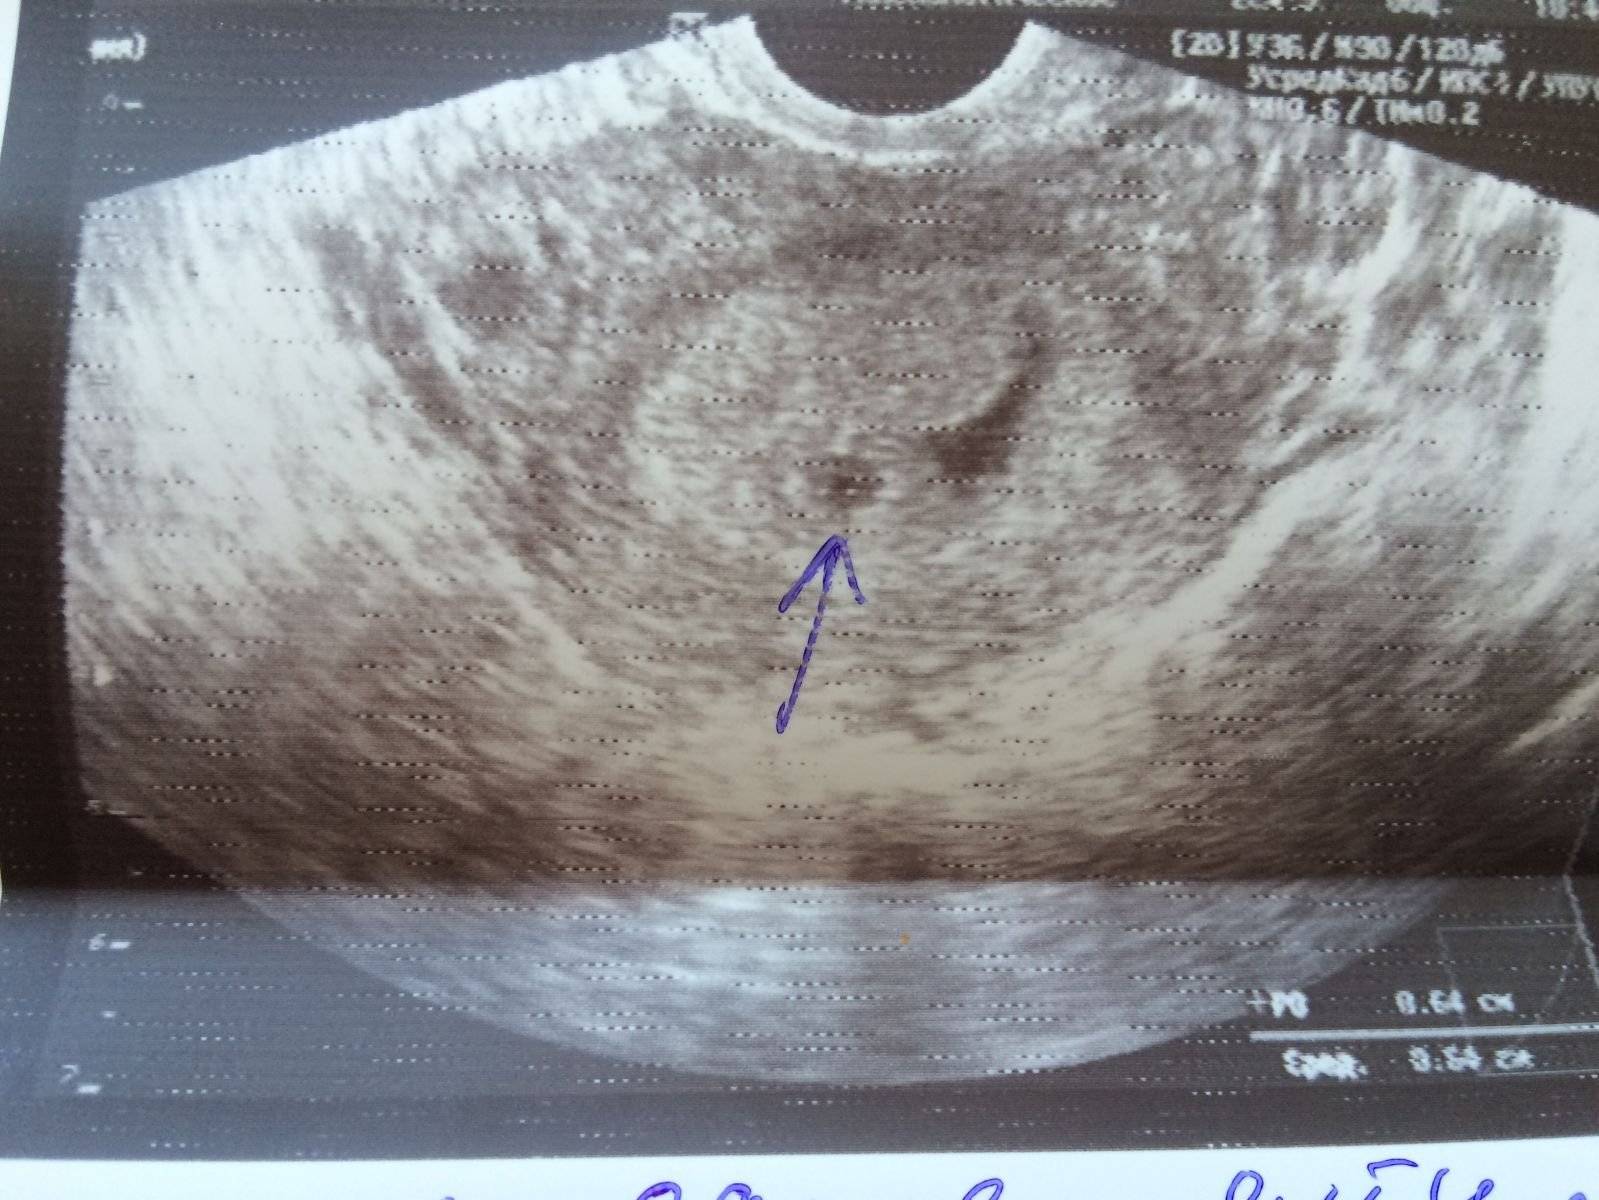

Фото Второй Беременности

Фото Второй Беременности 117 фотографий